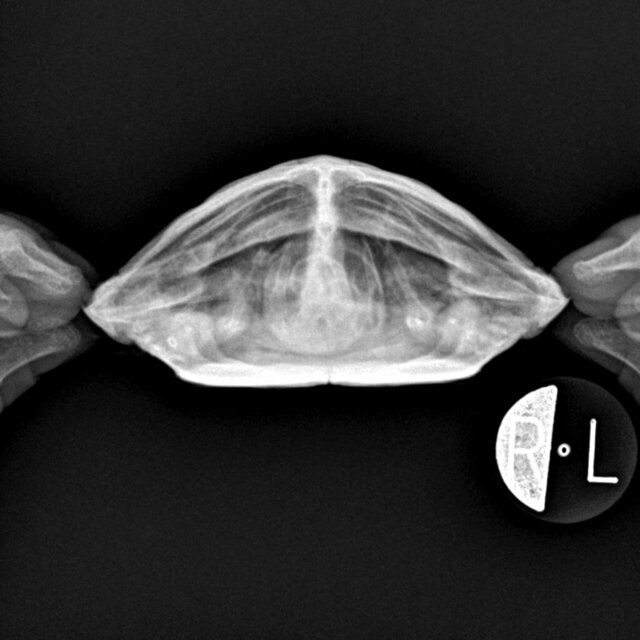

Михаил 1 Ваше имя: Звёздочка Локация: Тверская обл. г. Конаково Опубликовано: 28 марта 2023 Автор Опубликовано: 28 марта 2023 Здравствуйте! Мы сделали снимки, кому их показать?

Консультанты moth Ваше имя: Мария Локация: Москва Опубликовано: 28 марта 2023 Консультанты Опубликовано: 28 марта 2023 @Михаил 1 приложите тут, я скину врачу-герпетологу

Михаил 1 Ваше имя: Звёздочка Локация: Тверская обл. г. Конаково Опубликовано: 28 марта 2023 Автор Опубликовано: 28 марта 2023 Хорошо, спасибо!

Консультанты moth Ваше имя: Мария Локация: Москва Опубликовано: 28 марта 2023 Консультанты Опубликовано: 28 марта 2023 @Михаил 1 врач ответила, что ни пневмонии ни тимпании (вздутия жкт) у черепахи нет и по внешнему виду нет классических признаков авитаминоза. К сожалению тут может помочь только очный осмотр у хорошего герпетолога или хотя бы найти того, кто сможет взять кровь на анализ, т.к. иначе диагноз поставить невозможно. Врач предположила, что могут быть проблемы с печенью, т.к. это следующее по распространенности заболевание из-за неполноценного рациона с подобными симптомами.